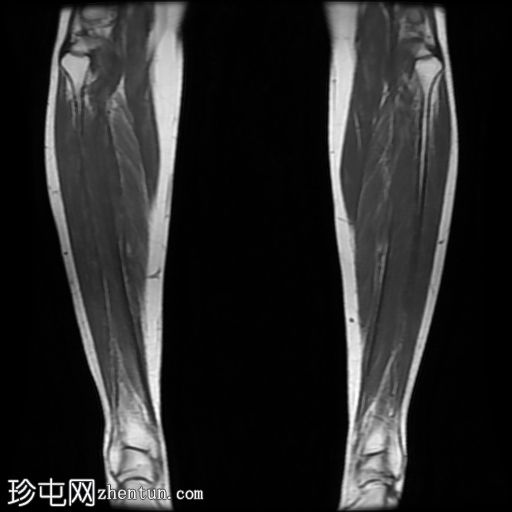

MRI

冠状位

T2加权像

内侧皮质可见一条低信号斜向皮质内线状影。

多发局灶性皮质内T2/STIR高信号病灶。皮质内可见一条线状信号异常区域。

邻近髓腔内广泛的骨髓水肿。

胫骨内侧缘骨膜水肿。